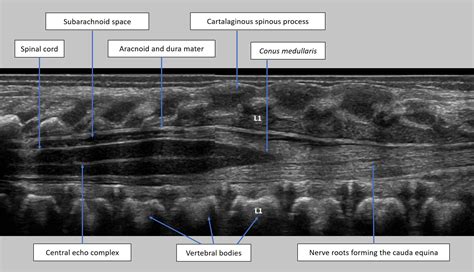

If your pediatrician determines that the dimple appears suspicious or "complex," they will likely recommend an ultrasound of the lower spine. This is a non-invasive, painless procedure that does not involve radiation. It uses sound waves to provide an image of the underlying structures of the spine to ensure everything is developed correctly.